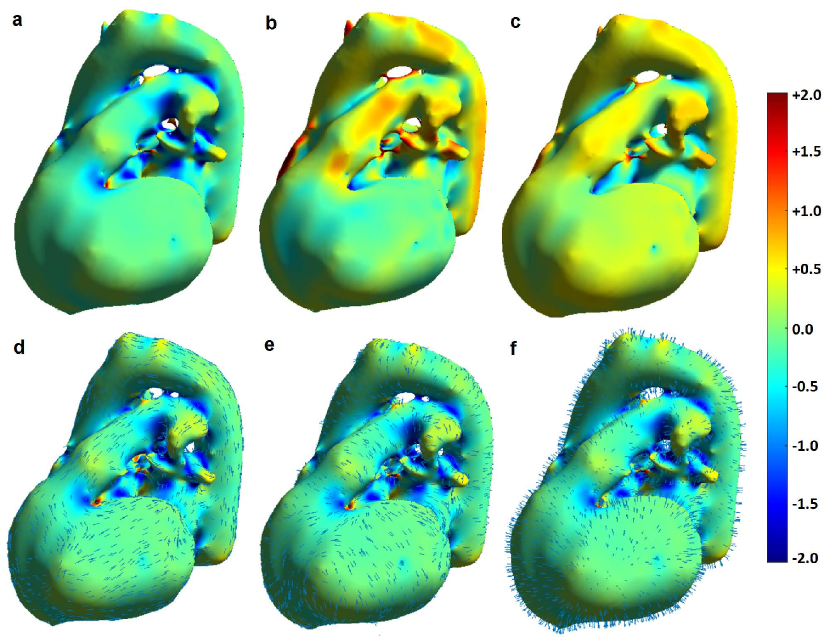

Figure 8 shows color-coded curvatures and directions of normals and minimum and maximum curvatures of the surface of a cardiac structure segmented over a volumetric water image. Among the introduced curvatures, the maximum curvature had the maximum variance and could thereby capture most of the shape variations over a surface.